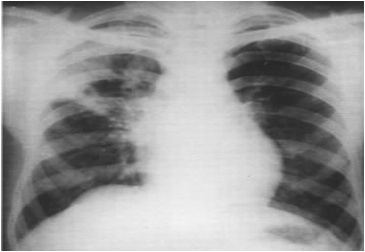

X线检查:原发综合征

哑铃状双极影:肺部原发病灶、淋巴结炎、淋巴管炎

支气管淋巴结结核

三种类型:

炎症型:表现为肺门影扩大,密度增高,边缘模糊;

结节型:肺门区出现圆形或卵圆形致密影,边缘清楚;

微小型:特点为肺纹理紊乱,肺门形态异常,肺门周围有小结节状及小点片状模糊影。

X线检查:支气管淋巴结结核

肺门影增浓